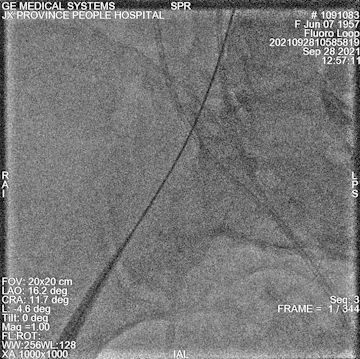

瓣膜定位

释放后

后扩

球扩后左冠开口到左冠瓣距离

最终造影

术中情况:术中超声及造影评估,左冠灌注未受影响,瓣膜释放后无明显下滑,洪浪院长术中使用VitaFlow Liberty™进行操作,并精准释放,超声及时辅助评估,VitaFlow二代可回收功能给术者增加信心,可以更放心、大胆的挑战高风险病例。